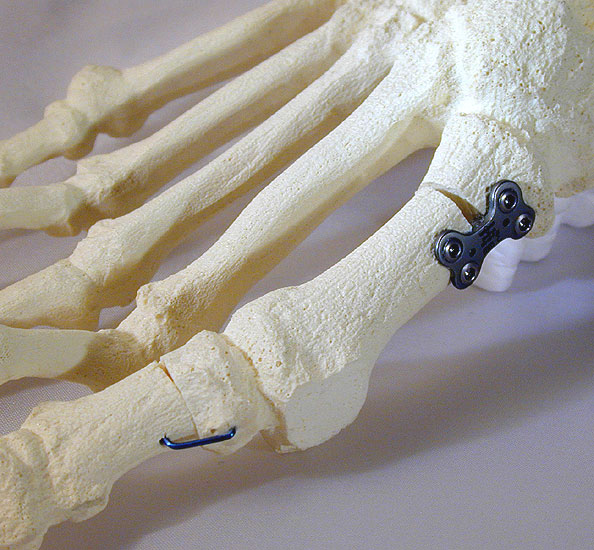

Instrumentarium für die open wedge Basisosteotomie.

Abbildung 2

• Kleines Fußinstrumentarium.

• Herstellerspezifisches Plattensieb und Osteosynthesen für ergänzende Korrekturen (z.B. Axomed Pedus-O® (Abb. 2.) -Axomed GmbH, Heinrich-von-Stephan-Str. 5c, 79100 Freiburg; Darco MFS® - DARCO GmbH & Co. KG, Gewerbegebiet 18, D82339 Raisting; Merete® - Merete Medical GmbH, Alt-Lankwitz 102, 12247 Berlin usw.).